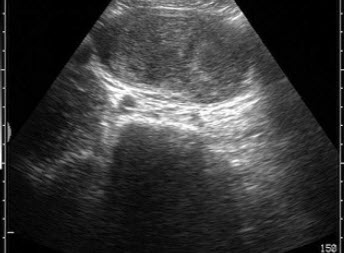

11、单项选择题

患者女47岁,皮肤、巩膜黄染,进行性加重2个月余,腹痛、腹胀,既往有胆结石病史。B超检查如图所示,根据超声声像图,诊断为()